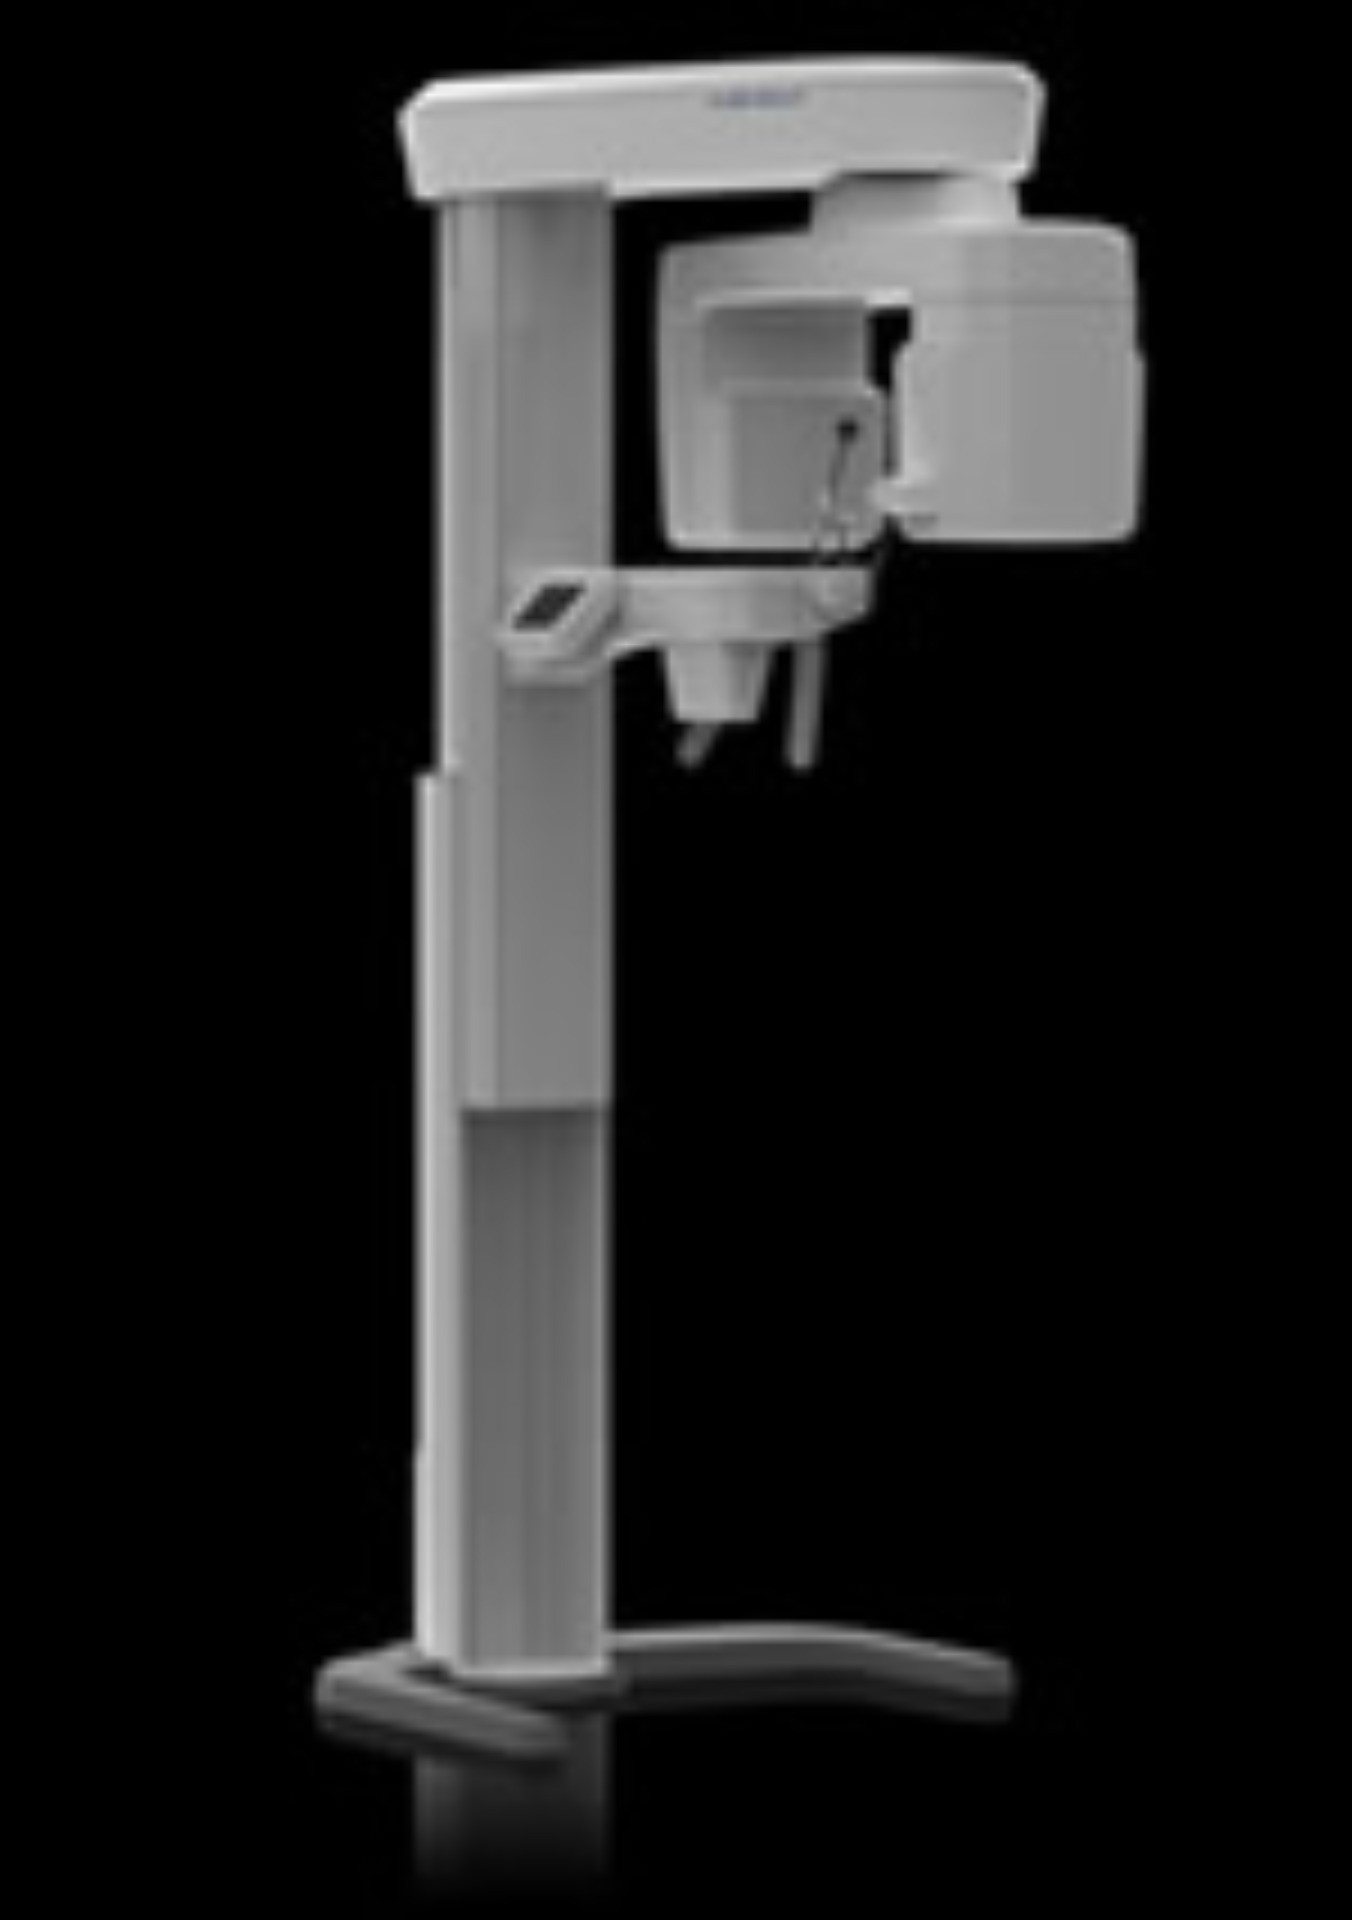

さらに新しい感動を AUGE-SOLIO

阿部歯科導入の歯科用CT「AUGE(オージェ)SOLIO」は、歯科用レントゲンにおいて、早くからCTの開発研究に取り組み、今までにも高精細画質な歯科CT装置を開発している(株)朝日レントゲン工業の最新鋭CTです。

阿部歯科導入の歯科用CT「AUGE(オージェ)SOLIO」は、歯科用レントゲンにおいて、早くからCTの開発研究に取り組み、今までにも高精細画質な歯科CT装置を開発している(株)朝日レントゲン工業の最新鋭CTです。